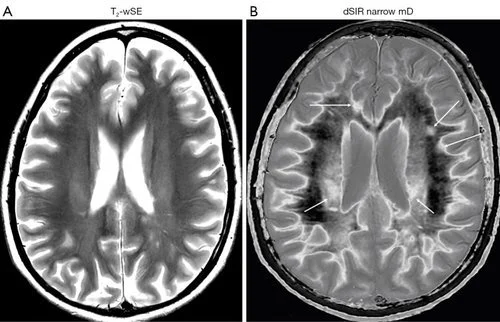

• Mātai Medical Research Institute - In one of our current projects we are collaborating with researchers at the Mātai Medical Research Institute, the University of Auckland, and the University of California San Diego regarding their medical imaging sequences MASDIR. In work that they have recently published you can see very subtle effects from the presence of multiple sclerosis on the left using a traditional T2-weighted sequence, and the very pronounced effects on the right using their new MASDIR sequence. The work that we are doing at Insight focuses on the mathematical modelling used to create these kinds of images.

Ma et al., Quant Imaging Med Surg 2022